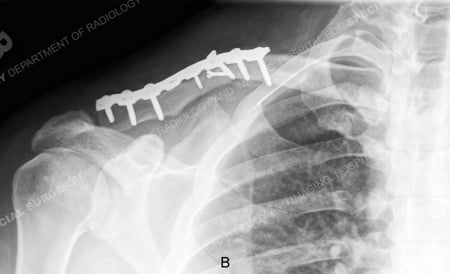

A 36-year-old male fell while skiing and sustained a right-sided displaced comminuted mid-shaft clavicle fracture. He presented to Dr. David L. Helfet at the HSS Orthopedic Trauma Service with ecchymosis and bruising near the fracture site and paresthesia in his right hand appearing to originate in the posterior radial nerve distribution without motor weakness. Operative reduction and internal fixation was performed with placement of a contoured 3.5 mm pelvic reconstruction plate. He continues to return for regular follow-up and at 10 weeks radiographs show a healing clavicle fracture with maintenance of reduction and fixation and presents with paresthesia symptoms.

X-ray taken at 10 weeks reveal a healing clavicle fracture.